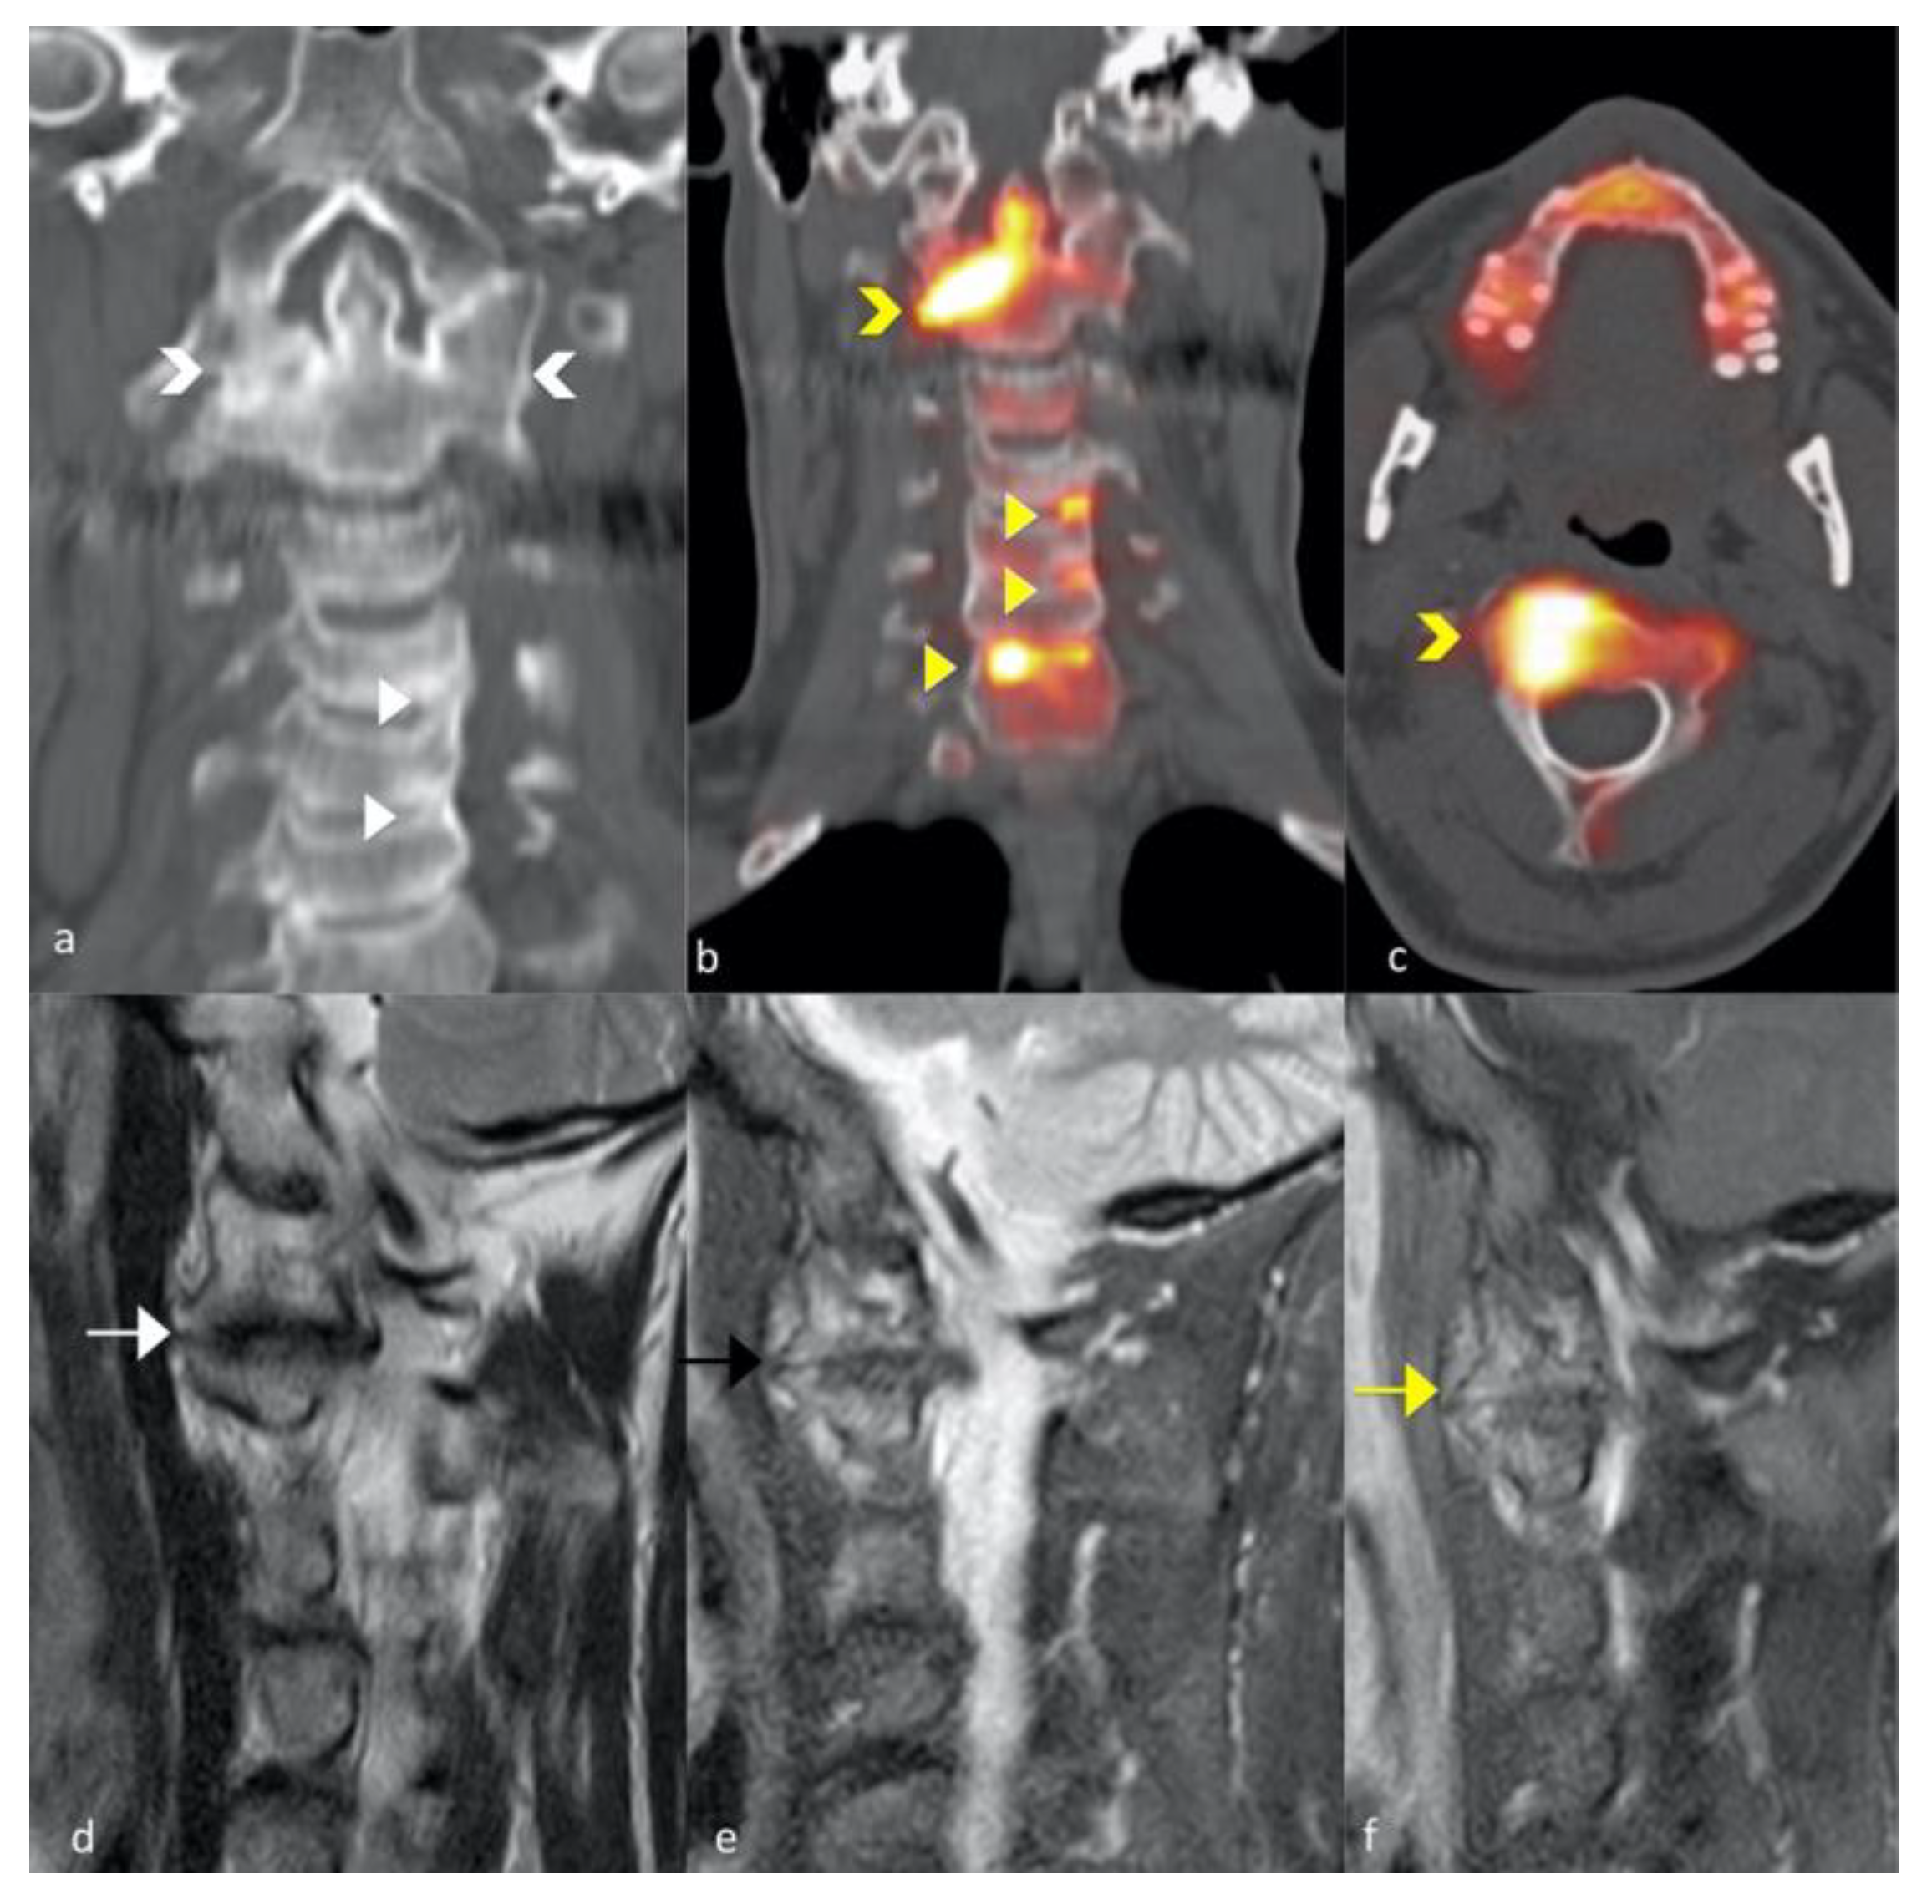

3.2. Magnetic Resonance Imaging Changes

3.3. FNa 18 PET CT

- Castillo-Gallego, C.; Aydin, S.Z.; Emery, P.; McGonagle, D.G.; Marzo-Ortega, H. Magnetic resonance imaging assessment of axial psoriatic arthritis: Extent of disease relates to HLA-B27. Arthritis Rheum. 2013, 65, 2274–2278. [Google Scholar] [CrossRef]

- Hermann, K.-G.A.; Baraliakos, X.; van der Heijde, D.M.F.M.; Jurik, A.-G.; Landewé, R.; Marzo-Ortega, H.; Østergaard, M.; Rudwaleit, M.; Sieper, J.; Braun, J.; et al. Descriptions of spinal MRI lesions and definition of a positive MRI of the spine in axial spondyloarthritis: A consensual approach by the ASAS/OMERACT MRI study group. Ann. Rheum. Dis. 2012, 71, 1278–1288. [Google Scholar] [CrossRef] [Green Version]

- Raynal, M.; Bouderraoui, F.; Ouichka, R.; Melchior, J.; Morel, O.; Blum, A.; Chary-Valckenaere, I.; Ngueyon Sime, W.; Roch, V.; Maksymowych, W.; et al. Performance of 18F-sodium fluoride positron emission tomography with computed tomography to assess inflammatory and structural sacroiliitis on magnetic resonance imaging and computed tomography, respectively, in axial spondyloarthritis. Arthritis Res. Ther. 2019, 21, 119. [Google Scholar] [CrossRef] [Green Version]